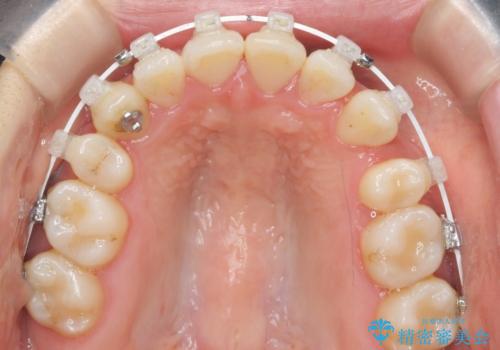

八重歯 上下の正中のずれ 40代で抜歯矯正

- 八重歯と上下の正中のずれを気にして来院。

上の前歯の正中が右にずれていました。

小臼歯抜歯を行い、ワイヤー矯正を行いました。

時間はかかりましたがしっかり治療することができました。